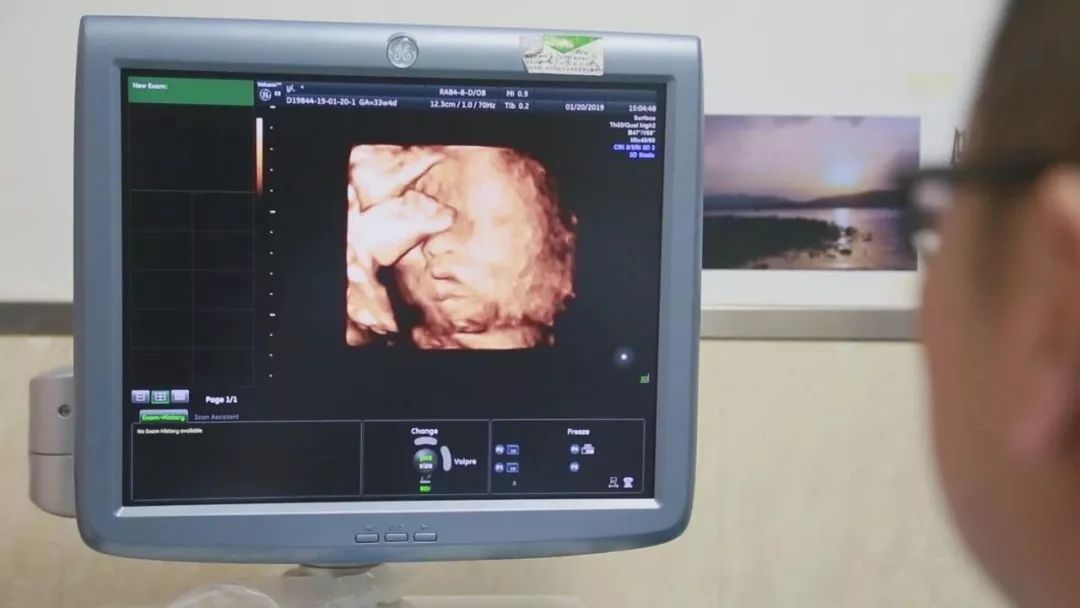

冷冻胚胎植入子宫孕育新生

在对移植子宫连续监测后,为提高胚胎移植成功率,专家团队采取中西医结合的方法,改善杨华子宫内膜情况,为胚胎着床做好准备。2018年6月13日,妇产科王西林教授实时监测超声,在超声“慧眼”精确指引下,妇产科黄艳红教授小心翼翼地将冷冻胚胎植入移植的子宫内。14天后,复苏胚胎着床,杨华成功妊娠,这已是第五次尝试。妊娠早期,杨华出现妊娠剧吐、先兆流产的症状,妊娠中晚期出现胎儿生长受限,先后4次住院进行保胎等治疗。

整个孕期,为避免出现并发症、确保母婴健康,妇产科、泌尿外科专家团队结合杨华身体情况,制定了个体化免疫抗排斥用药等方案,并定期进行超声、血药浓度、激素水平等监测。根据监测结果,实时调整用药,保证胎儿羊水、体重、胎心等生长发育指标处于正常范围。